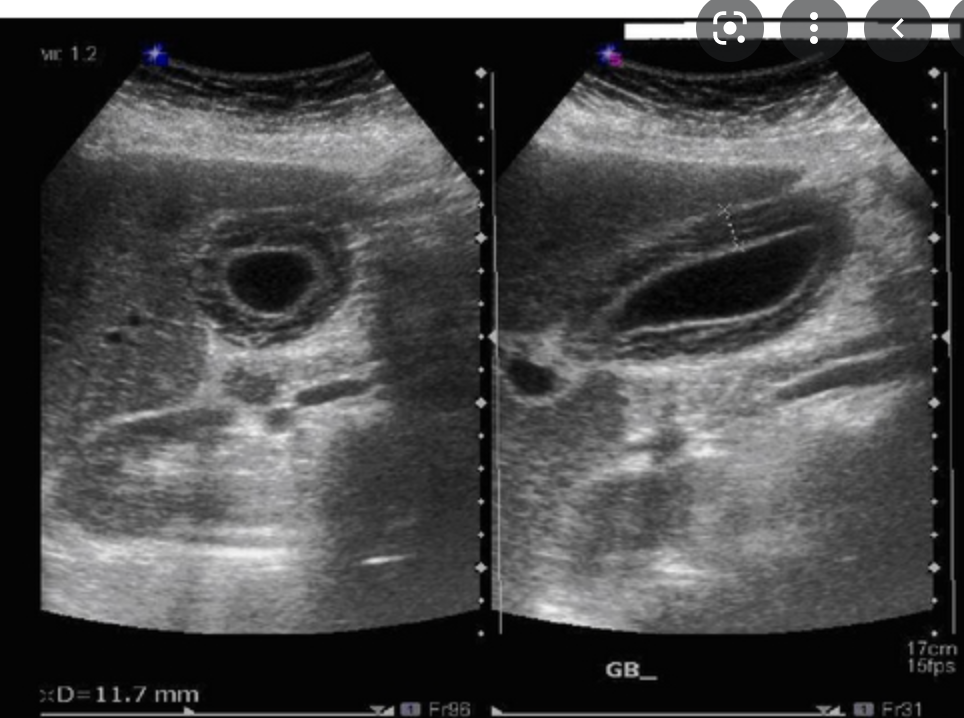

where is the CHD measured on US?

What are the normal measurements?

- CHD measurements (inner wall to inner wall) are performed at the level of the hepatic artery

- Normal measurements

- <7mm in normal fasting patients <60yo

- <10 mm in normal fasting patients >60yo

- <11mm in pts with previous

- surgery

- CBD obstruction

- Fatty meal challenge

- if CHD enlarges more than 2mm after fatty meal, it indicates obstruciton